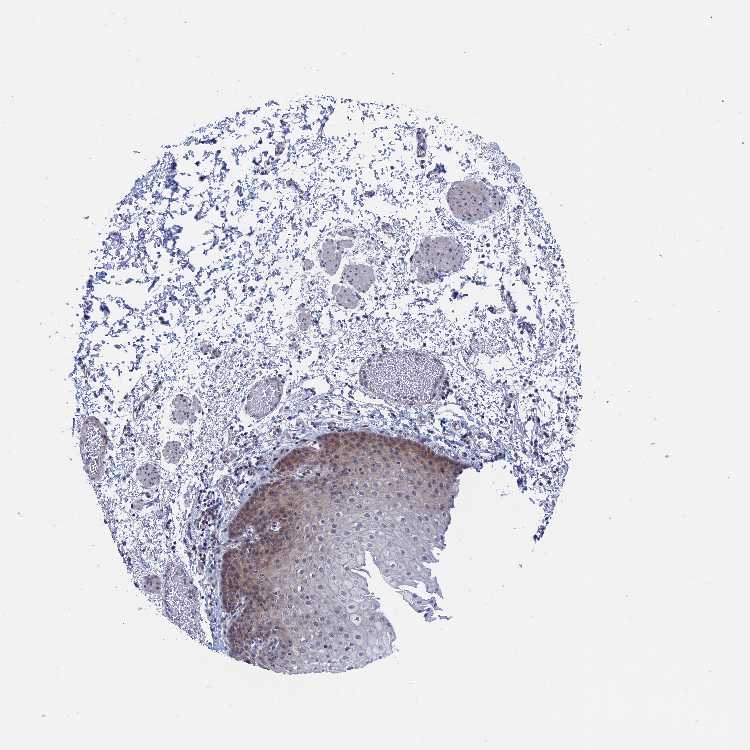

ESOPHAGUS - Antibody stainingi

Antibody staining in the annotated cell types in the current human tissue is reported as not detected, low, medium, or high, based on conventional immunohistochemistry profiling in selected tissues. This score is based on the combination of the staining intensity and fraction of stained cells.

Each image is clickable and will lead to virtual microscopy that enables deeper exploration of all samples and also displays staining intensity scores, fraction scores and subcellular localization as well as patient and tissue information for each sample.

Antibody HPA043406

Squamous epithelial cells Low